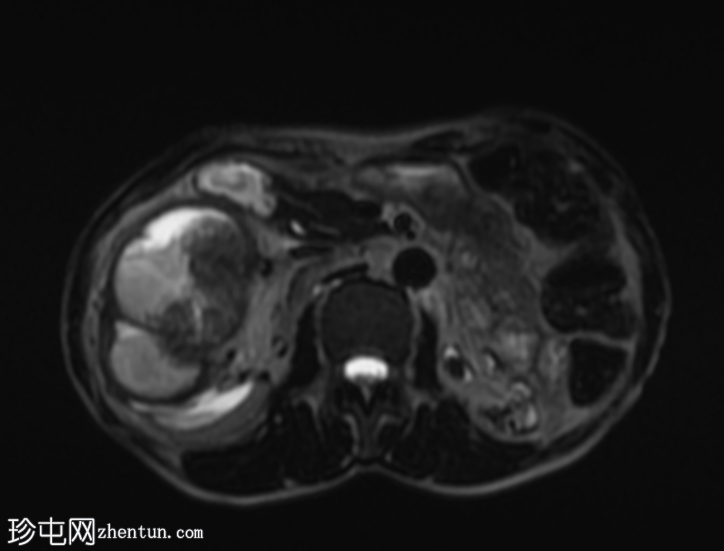

轴位

STIR序列

再次观察到上述肾前部外生性病变,其实性成分在T1加权像上呈等高信号,在T2加权像上呈低信号,伴有碎片扩散受限和低ADC值(化脓性物质)。囊性成分内部可见液-碎片/脓液界面。可见内部低信号结石。可见肾周模糊影。该病变压迫并可能侵犯右肾盂,导致中度肾积水。

病灶不规则的低信号,以及液-液界面伴有碎屑(可能为化脓性物质)扩散受限和肾周模糊,再次高度提示炎症性病变(黄色肉芽肿性肾盂肾炎,XGP),而非可能性较小的肿瘤。